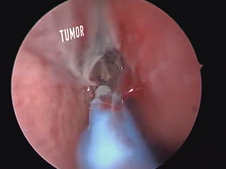

Microdirect Laryngoscopy with CO2 Laser Wedge Excisions for Subglottic Stenosis

- Date : 01/01/2020